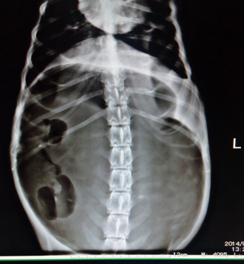

沈阳动物医院一只德国牧羊犬,母,一岁,免疫全,30kg

早上正常采食,半小时后出现喘气急促,腹部膨胀,敲击出现鼓音。

随即带到医院检查,怀疑是急性胃扩张或者扭转。由于当地医院条件有限,主人从梅河口开车来沈阳就医。

下面是来我院时拍的x-ray,

随即立刻进行手术治疗,复位扭转的胃,同时导出大量液性食糜,复位后又做的肋骨固定,术后三天进食,七天拆线。 犬急性胃扩张是指胃内容物不能正常排空,使胃内充满气体、液体和食物,引起多组织器官受损一种突发性的、剧烈的致命性胃肠道疾病。 很多品种的犬都能发生,一般影响大型、深胸品种的犬。最常见品种犬有大丹犬、德国牧羊犬、标准贵妇犬、圣伯纳犬。 所有年龄的犬都可以发生,但是老龄犬的发病率更高。